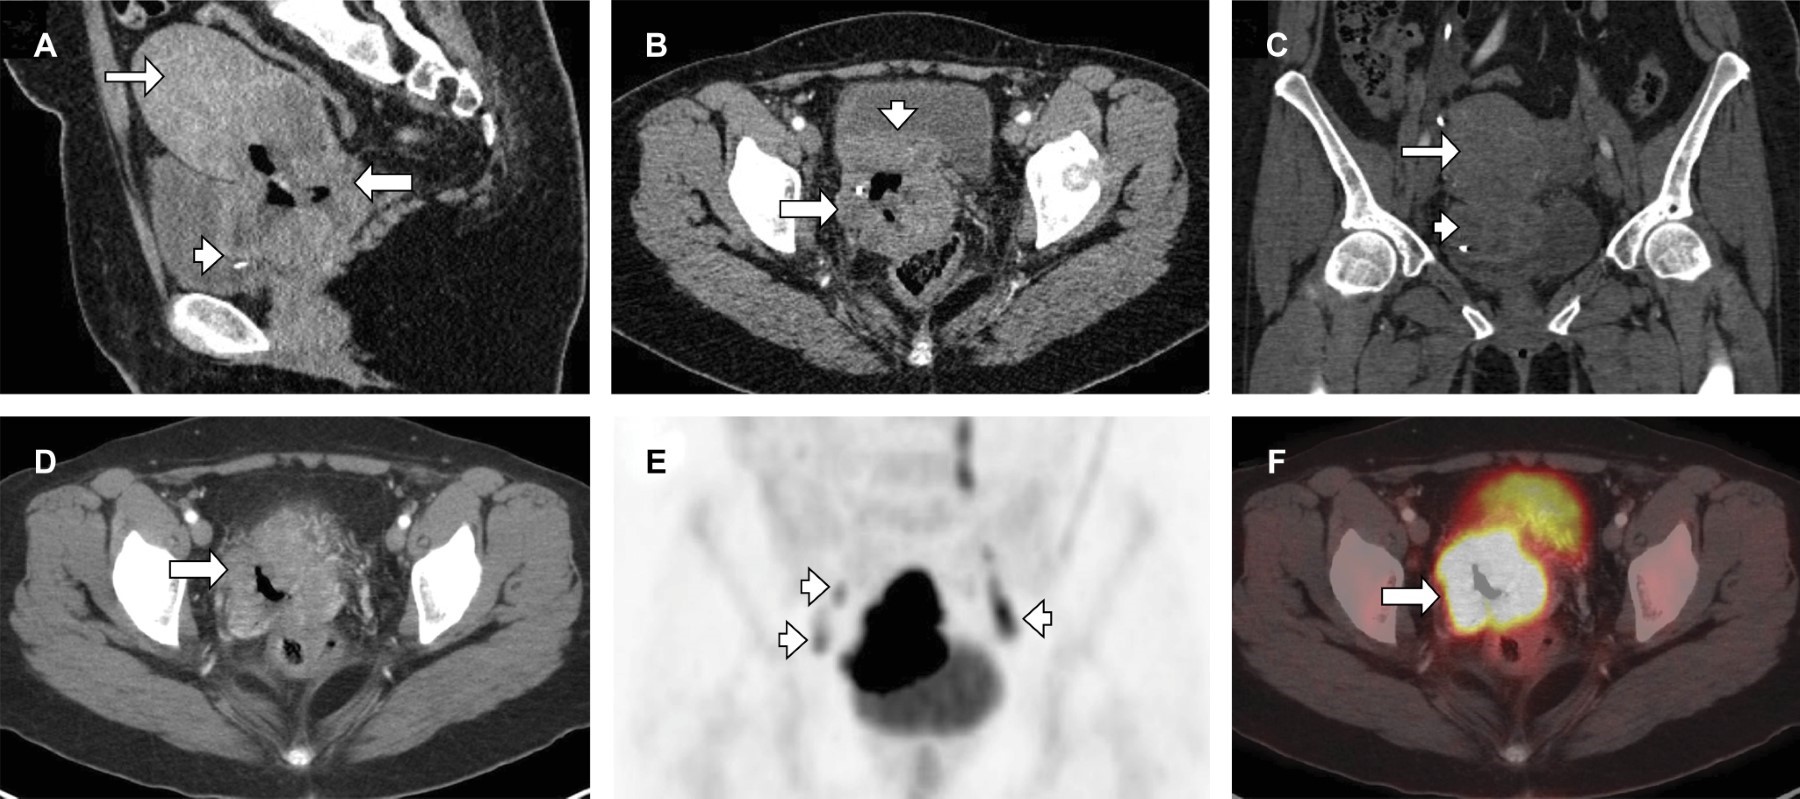

Paciente femenino de 39 años, sin antecedentes personales ni familiares relevantes, diagnosticada con carcinoma cervicouterino epidermoide hace seis meses; presenta datos de choque hemorrágico. En la exploración física dirigida, se identifica una tumoración ulcerada de 7 cm en el cuello uterino con invasión vaginal y sangrado activo. Los estudios de laboratorio e imagen muestran: hemoglobina (Hb) 5.9 y tumoración dependiente del cérvix con infiltración hacia la vejiga, estadio IV A (Figura 1). Dadas las opciones terapéuticas limitadas, se realiza una embolización de arterias uterinas (Figuras 2 y 3), que resultó exitosa en el control del sangrado.

Figura 1